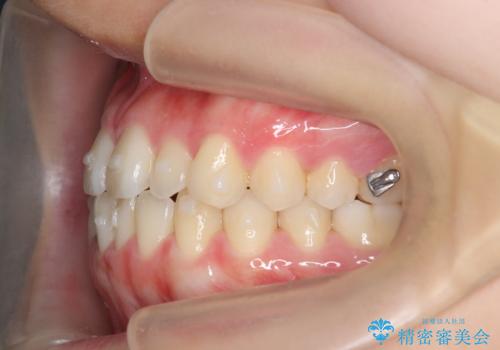

ガタつきの改善 マウスピース矯正治療

- 歯のがたつきの改善を求めて、矯正治療を希望され来院されました。

少量の歯のディスキング、歯列弓拡大、アタッチメントを装着することで審美的な歯列へとマウスピース矯正インビザラインを用いて治療を行います。

マウスピース矯正は装着時間の遵守が非常に大切ですが、しっかりと20時間/日以上の装着を守っていただいたおかげで良好な治療結果を得ることができました。